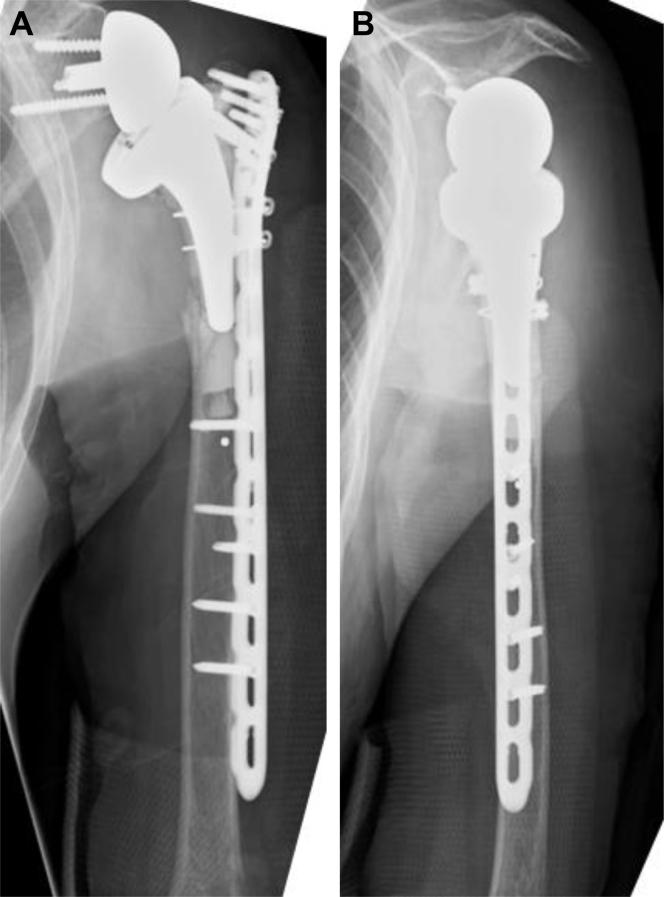

PHILOS plating of periprosthetic humeral shaft fracture after onlay-type reverse total shoulder arthroplasty: a case report.

JSES Rev Rep Tech. 2020 Dec 11;1(1):65-68. doi: 10.1016/j.xrrt.2020.11.003. eCollection 2021 Feb.